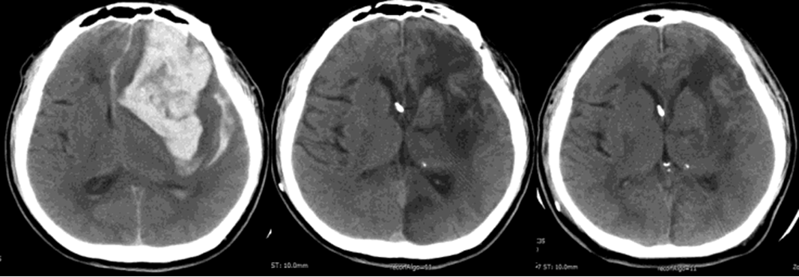

脑卒中是急性脑血管疾病统称:分脑血管破裂出血(如脑出血)和血管阻塞致供血中断(如脑梗塞),均损伤脑组织,且发病急、进展快、后果重,后遗症含瘫痪、语言障碍等,给个人、家庭和社会带来重负。

随后他接受了脑室间充质干细胞移植:3 周后首次移植,1 个月、2 个月时再次移植,全程无不良反应。随访结果令人惊喜:3 个月、6 个月、12 个月时,他的 NIHSS(国家卫生研究所卒中量表)评分从 23 分分别降至 20 分、19 分、19 分;12 个月时,他已能坐在轮椅上,成功脱离气管切开管和鼻胃管,影像学还显示枕部梗死面积和血肿周围低密度区域明显缩小。